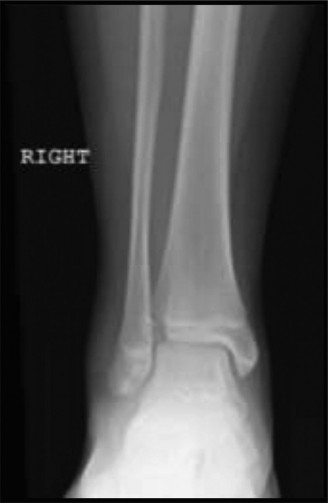

The initial anteroposterior (AP) and lateral radiographs of the right femur demonstrate a complete, displaced, length-stable transverse fracture of the middle third of the femoral diaphysis. There is minimal comminution. The traction splint has effectively restored length, though there remains slight apex-lateral and apex-anterior angulation.

Crucially, dedicated AP and lateral views of the right hip and right knee are obtained. The femoral neck is intact, with no evidence of a basicervical or transcervical fracture—a classic "missed injury" in the setting of high-energy femoral shaft fractures. The distal femoral physis is open and symmetric, with no widening or displacement to suggest a concurrent Salter-Harris injury.

In our patient, the history of a high-energy tackle in an active 7-year-old perfectly aligns with a traumatic diaphyseal fracture. The radiographs confirm normal bone density and morphology, ruling out a pathological etiology. Her age and the witnessed mechanism effectively rule out NAT.